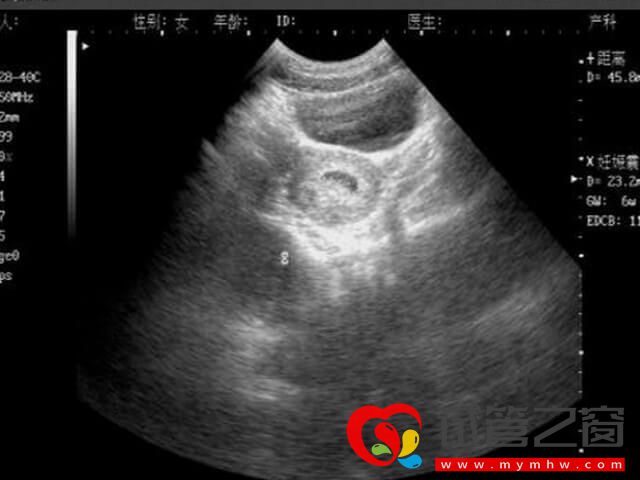

胎盤低指胎盤附著在子宮下段接近宮頸口位置,且胎盤邊緣距子宮頸內口不足2㎝的情況,屬于前置胎盤的一種。對于利用試管技術助孕的女女性來說,若是存在以下情況,就容易導致胎盤低置,反之就不容易出現: